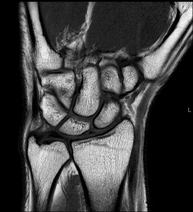

- Wrist / carpus MRI

Examination to study injuries to tendons, muscles and joints. Very useful for assessing minor, otherwise unnoticed fractures, ligament injuries, and inflammatory and degenerative processes (arthritis and osteoarthritis). It lasts approximately 20 minutes. It is a radiation-free procedure.